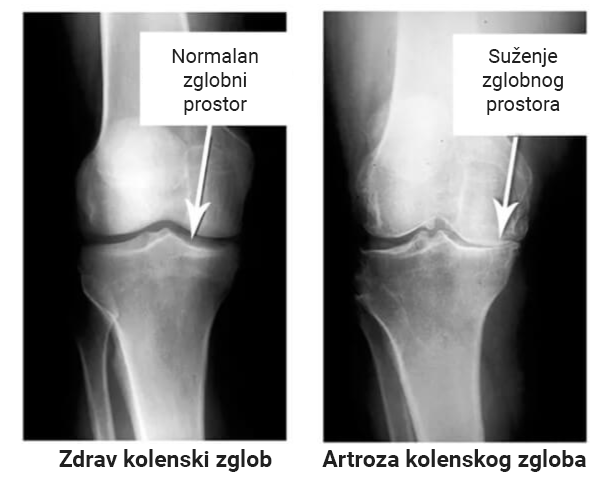

Pogledajte ove slike, možete videti da na desnoj slici nema zglobnog prostora, kosti se trljaju jedna o drugu, izazivajući jak bol. I ovaj proces je veoma teško zaustaviti! Za par godina čovek će postati invalid i neće moći da se služi.